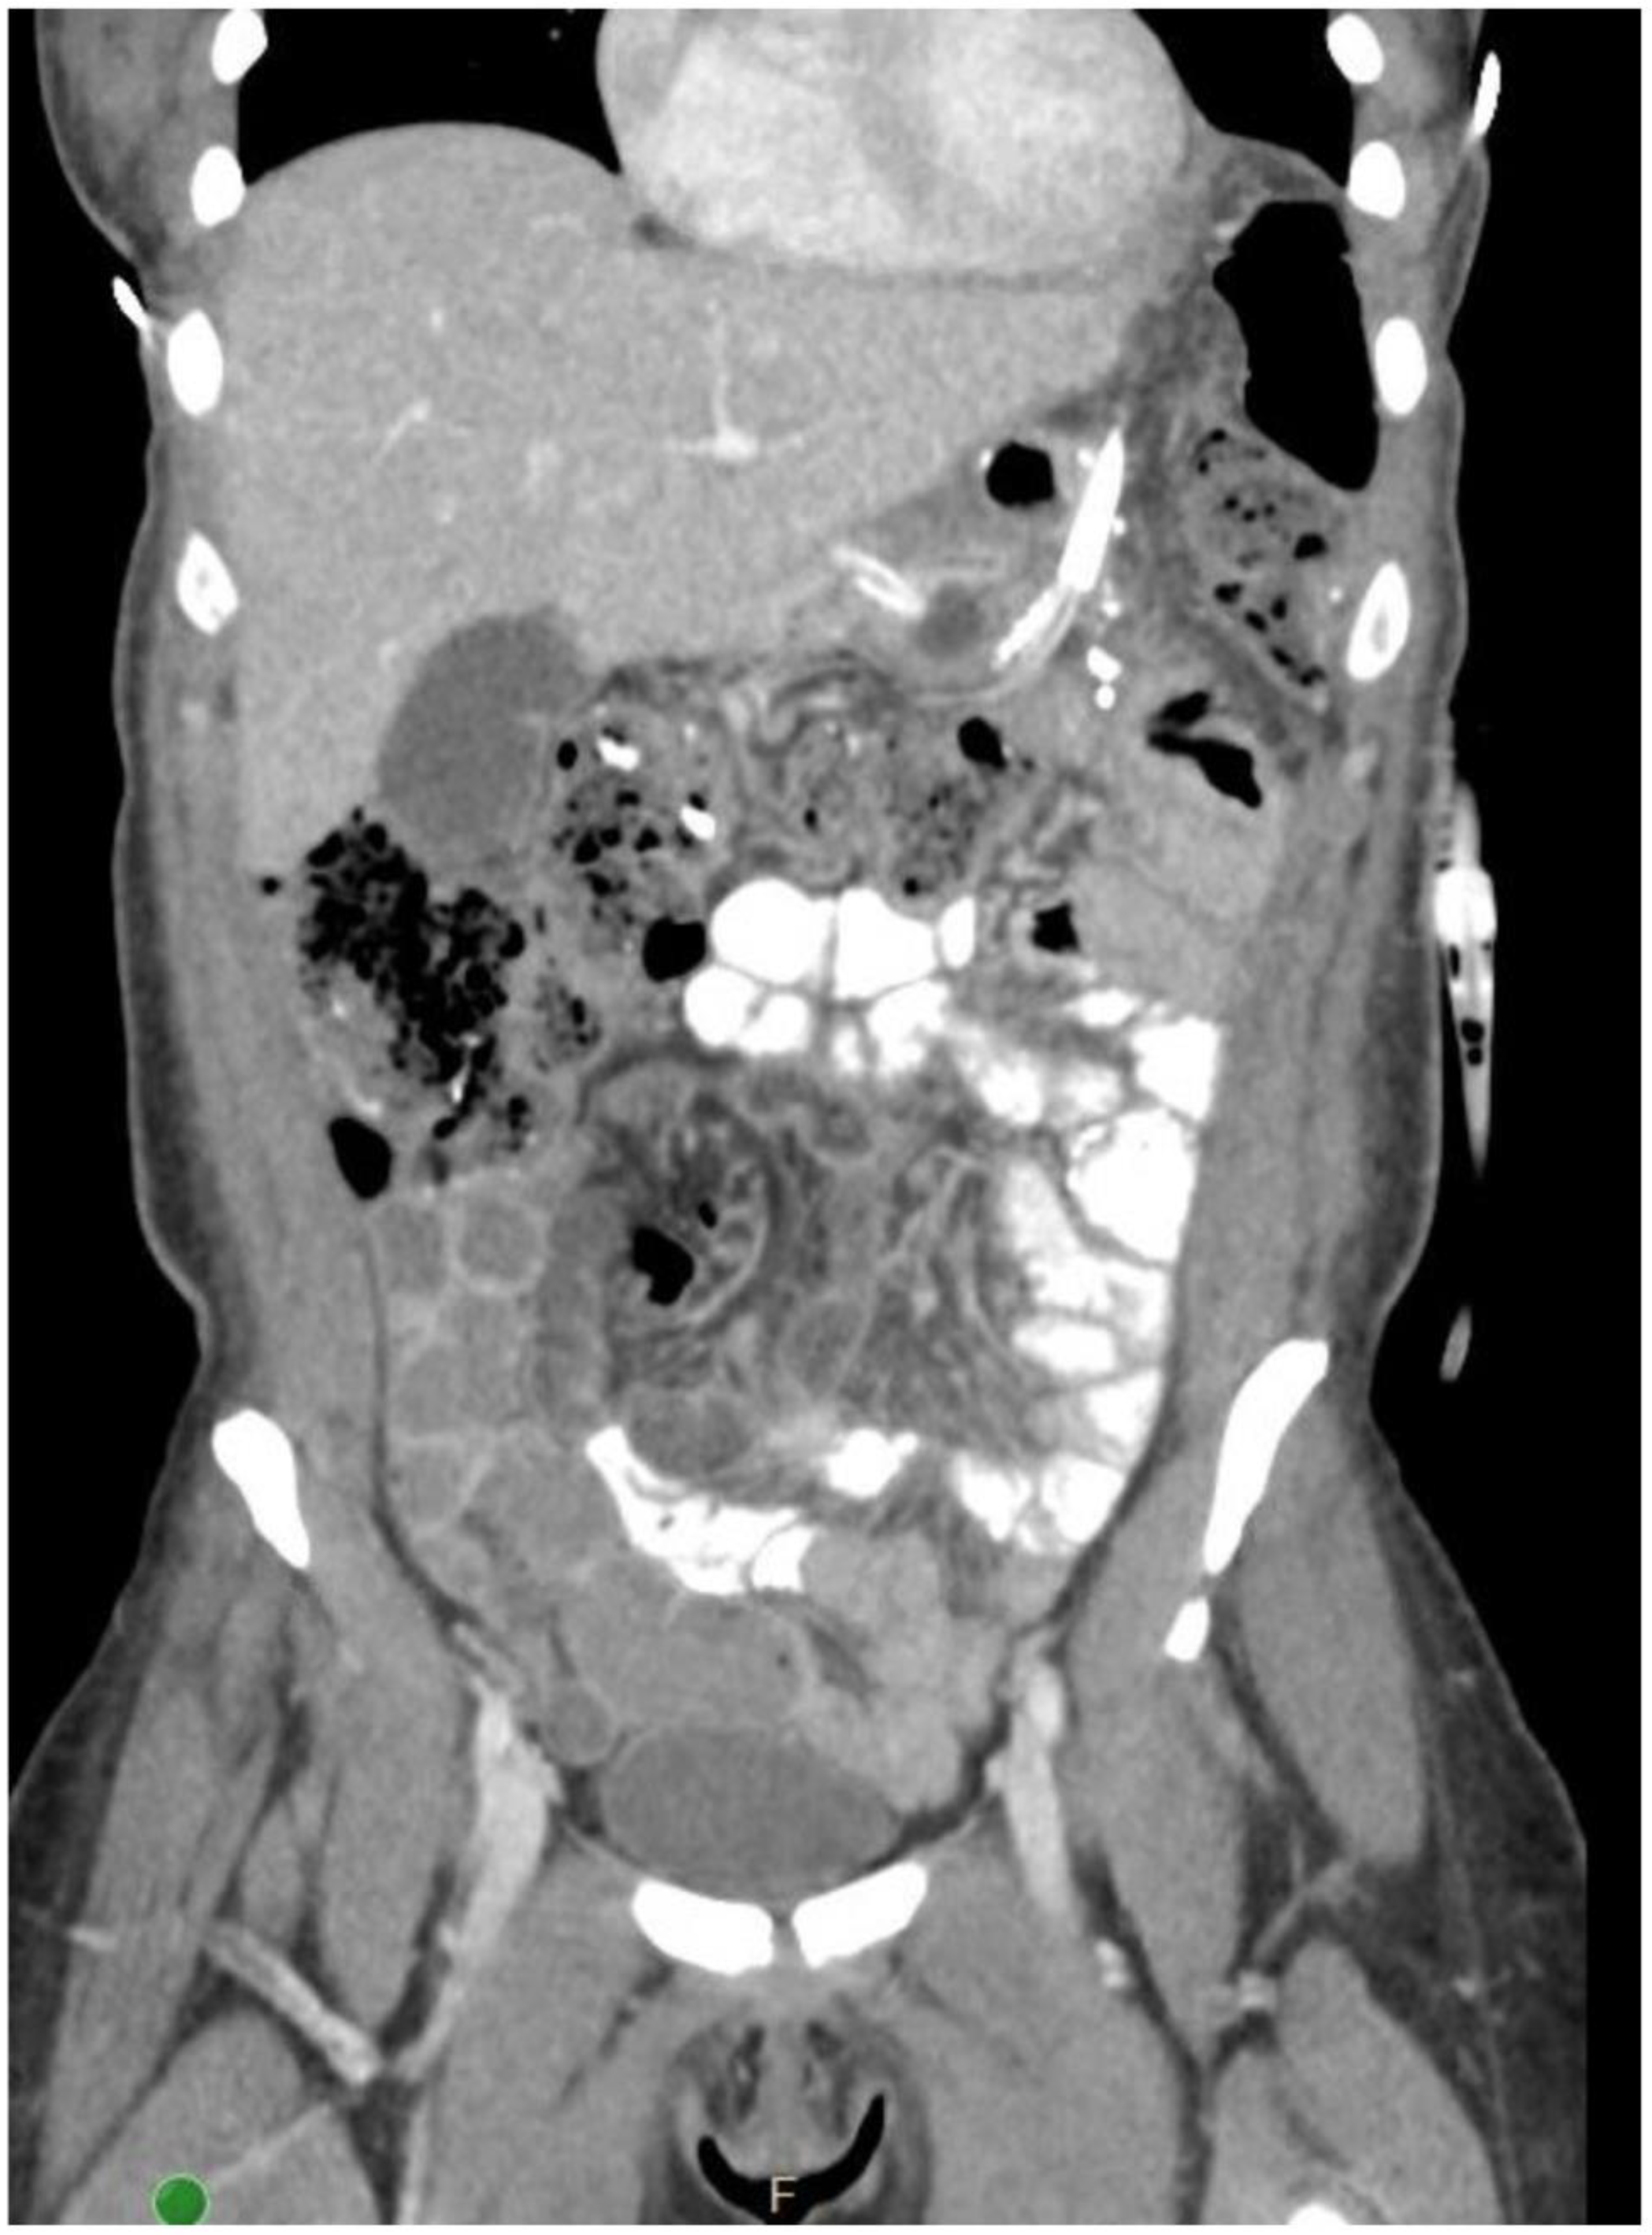

2. Detailed Case Description